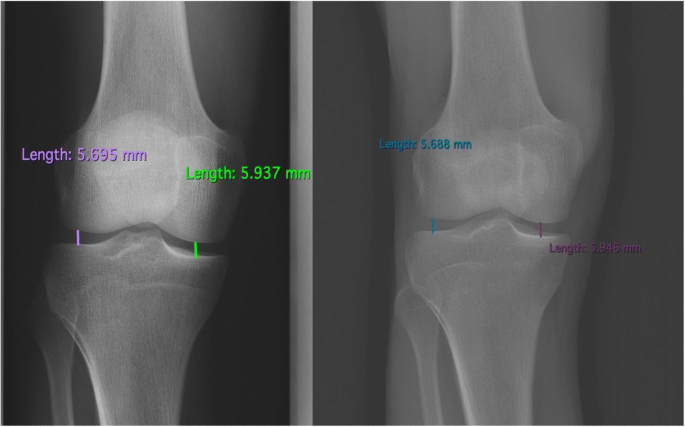

Whatsapp x WhatsApp Number Message phone x email x info@imagesradiologycom If you know, EOS is a low dose weight bearing XRay technology Images of the human body or the skeletal system can be produced in 2D or 3D form Contact us Home;The EOS Imaging System is a revolutionary advance in xray imaging Using Nobel Prizewinning technology, the ultralowdose system scans our patients in an upright, weightbearing position in seconds This allows the doctor to see the natural way that their joints interact with their musculoskeletal system, making it ideal for diagnosing

Eos x ray system-EOSedge EOSedge is a precise, low dose imaging system that delivers full body, highquality images covering the full set of musculoskeletal and orthopedic exams This next generation solution captures fully functional 2D/3D biplanar images in seconds, using a highresolution photoncounting detector for outstanding image quality for a broad range of patientsEOS imaging is a medical device company based in Paris, France, that designs, develops, and markets EOSedge and the EOS system, innovative, orthopedic medical imaging systems, associated with several orthopedic solutions along the patient care pathway – from diagnosis to postoperative treatments The EOS platform targets musculoskeletal disorders and orthopedic

The new EOS Xray system uses significantly lower radiation in the diagnosis of scoliosis Patients stand or sit inside the imaging system while it takes spAbstract Background EOS is a biplane Xray imaging system manufactured by EOS Imaging (formerly Biospace Med, Paris, France) It uses slotscanning technology to produce a highquality image with less irradiation than standard imaging techniques Objective To determine the clinical effectiveness and costeffectiveness of EOS twodimensional (2D)/threedimensional (3D) X The EOS™ Xray machine, based on a Nobel prizewinning invention in physics in the field of particle detection, is capable of a simultaneous capture of biplanar Xray images by slot scanning of the whole body in an upright, physiological loadbearing position, using ultralow radiation doses

EOS is highly efficient as this imaging system uses low does of radiation compared to the other MRIs It can give the physicians a better hand to preplan the treatment for the children which can bring out effective results An EOS scan can effectively show the child’s natural weight bearing posture and even allows us to see the interaction between joints and hips, spine and legs EOS Xrays produce highquality detailed images and expose patients to significantly lower doses of radiation than traditional Xrays “An EOS imaging system is important for kids with scoliosis because the radiation dose is about 1/7th of a normal Xray dose at the initial visit and much lower still for followup Xrays using the microdoseNo evidence was found on the impact of EOS on patients' pathways of care or ultimate health outcomes Radiation dose is considerably lower with EOS than CR or film Xray imaging, whereas image quality remains comparable or better with EOS Patient throughput is the major determinant of the costeffectiveness of EOS